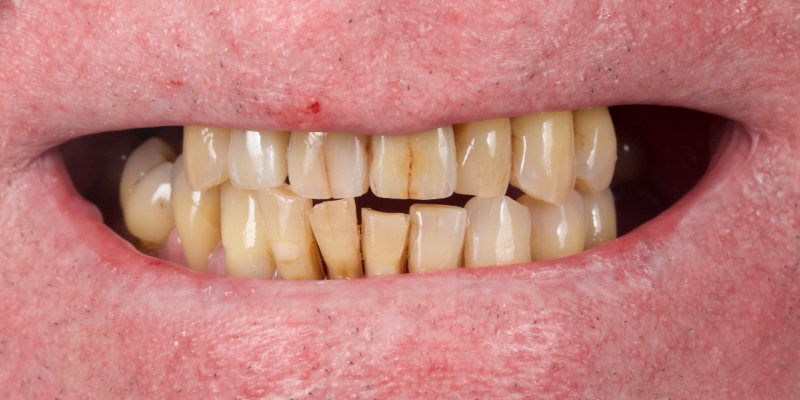

Here’s Elizabeth’s case. She had a periodontal lesion affecting the upper right central incisor (Fig. 13).

The tooth was extracted and a provisional nonprecious adhesive bridge with composite pontic was placed (Figs. 14-16).

The Rochette-type wing was placed on the lateral incisor abutment (Fig. 17). Grafting procedures were carried out before definitive restoration with a lithium disilicate adhesive bridge.